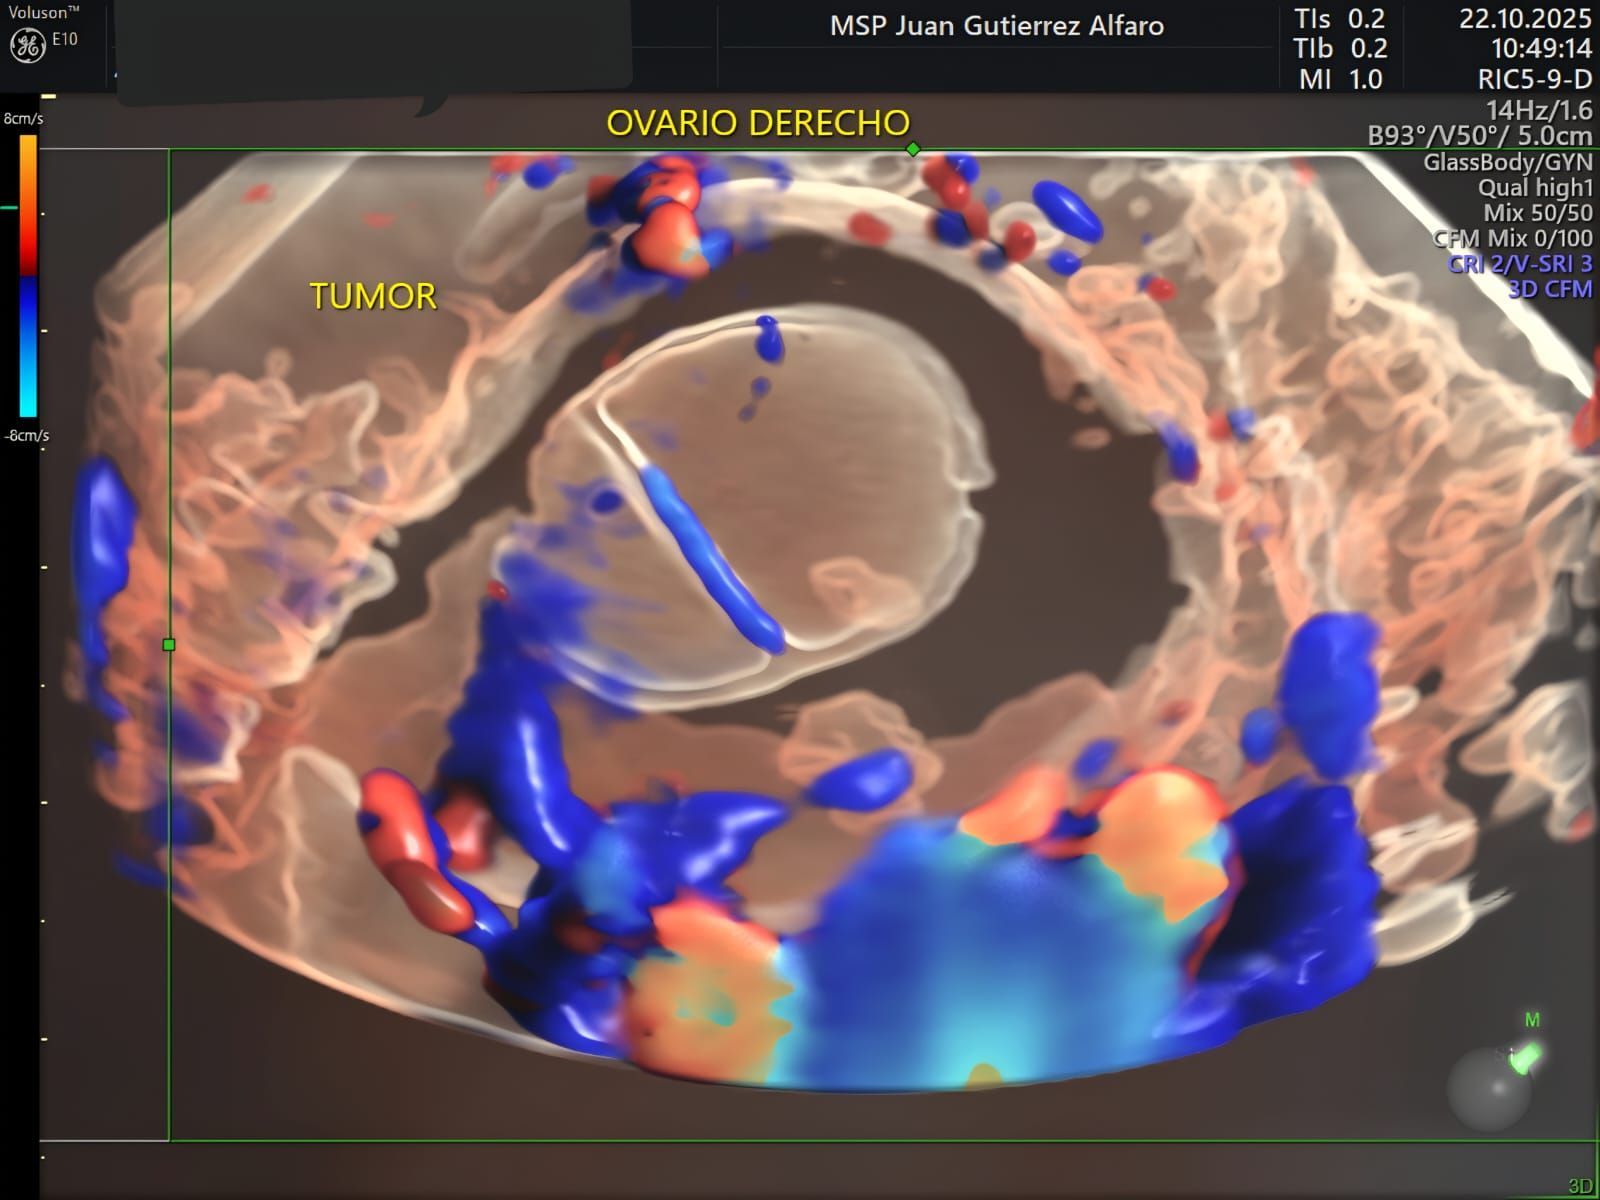

- Color Doppler – Radiantflow

- IOTA - International Ovarian Tumor Analysis

- HDlive Flow - Doppler